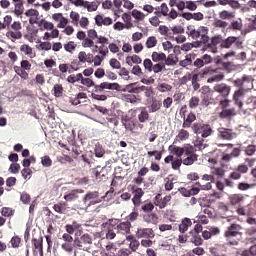

Setup. We evaluate all models on the Camelyon16 Whole Slide Image cancer detection dataset (Bejnordi et al., 2017). Each instance consists of a high resolution image of tissue from a medical scan which is pre-processed into patches of RGB pixels. After pre-processing, the average number of patches in a single set is over 9,300 (7.3GB), making each input roughly equivalent to processing 1% of ImageNet1k (Deng et al., 2009). The largest input in the training set contains 32,382 patches (25.4 GB). We utilize a ResNet18 (He et al., 2016) which is pretrained on Camelyon16 (Li et al., 2021) via SimCLR (Chen et al., 2020) as a backbone feature extractor whose weights can be downloaded from this repository111https://github.com/binli123/dsmil-wsi. Our goal is to first pretrain MBC set encoders on the extracted features, and then use the unbiased estimation of the full set gradient to fine-tune the feature extractor on the full input sets. We evaluate the performance of UMBC against non-MBC MIL baselines: DS-MIL (Li et al., 2021) and AB-MIL (Ilse et al., 2018), as well as MBC baselines: DeepSets and SSE.

The Camelyon16 Whole Slide Image dataset consists of 270 training instances and 129 validation instances. The dataset was created for a competition, and therefore the test set is hidden. We therefore follow the example set by previous works (Li et al., 2021) and report performance achieved on the validation set. For preprocessing, we consider the slide magnification setting, and use OTSU’s thresholding method to detect regions containing tissue within the WSI. We then split the activated regions into non overlapping patches of size . An example of single input patches can be seen in Figure 12. The largest input set contains image patches which are each . All patch extraction code can be found in the supplementary file. Table 14 contains statistics related to the numbers of patches per input for the training and the test set as well as the distribution of positive and negative labels.